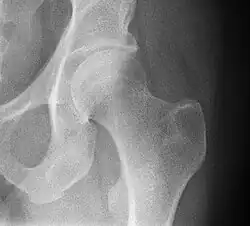

- Hip joint: AP and Lateral.[15]

- The Lauenstein projection a form of examination of the hip joint emphasizing the relationship of the femur to the acetabulum. The knee of the affected leg is flexed, and the thigh is drawn up to nearly a right angle. This is also called the frog-leg position.

-

AP view of normal hip -

Lauenstein projection of normal hips

- Applications include X-ray of hip dysplasia.